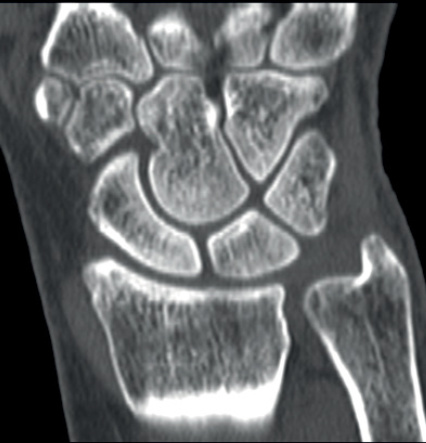

Image

Querschnitt durch das Gehirn